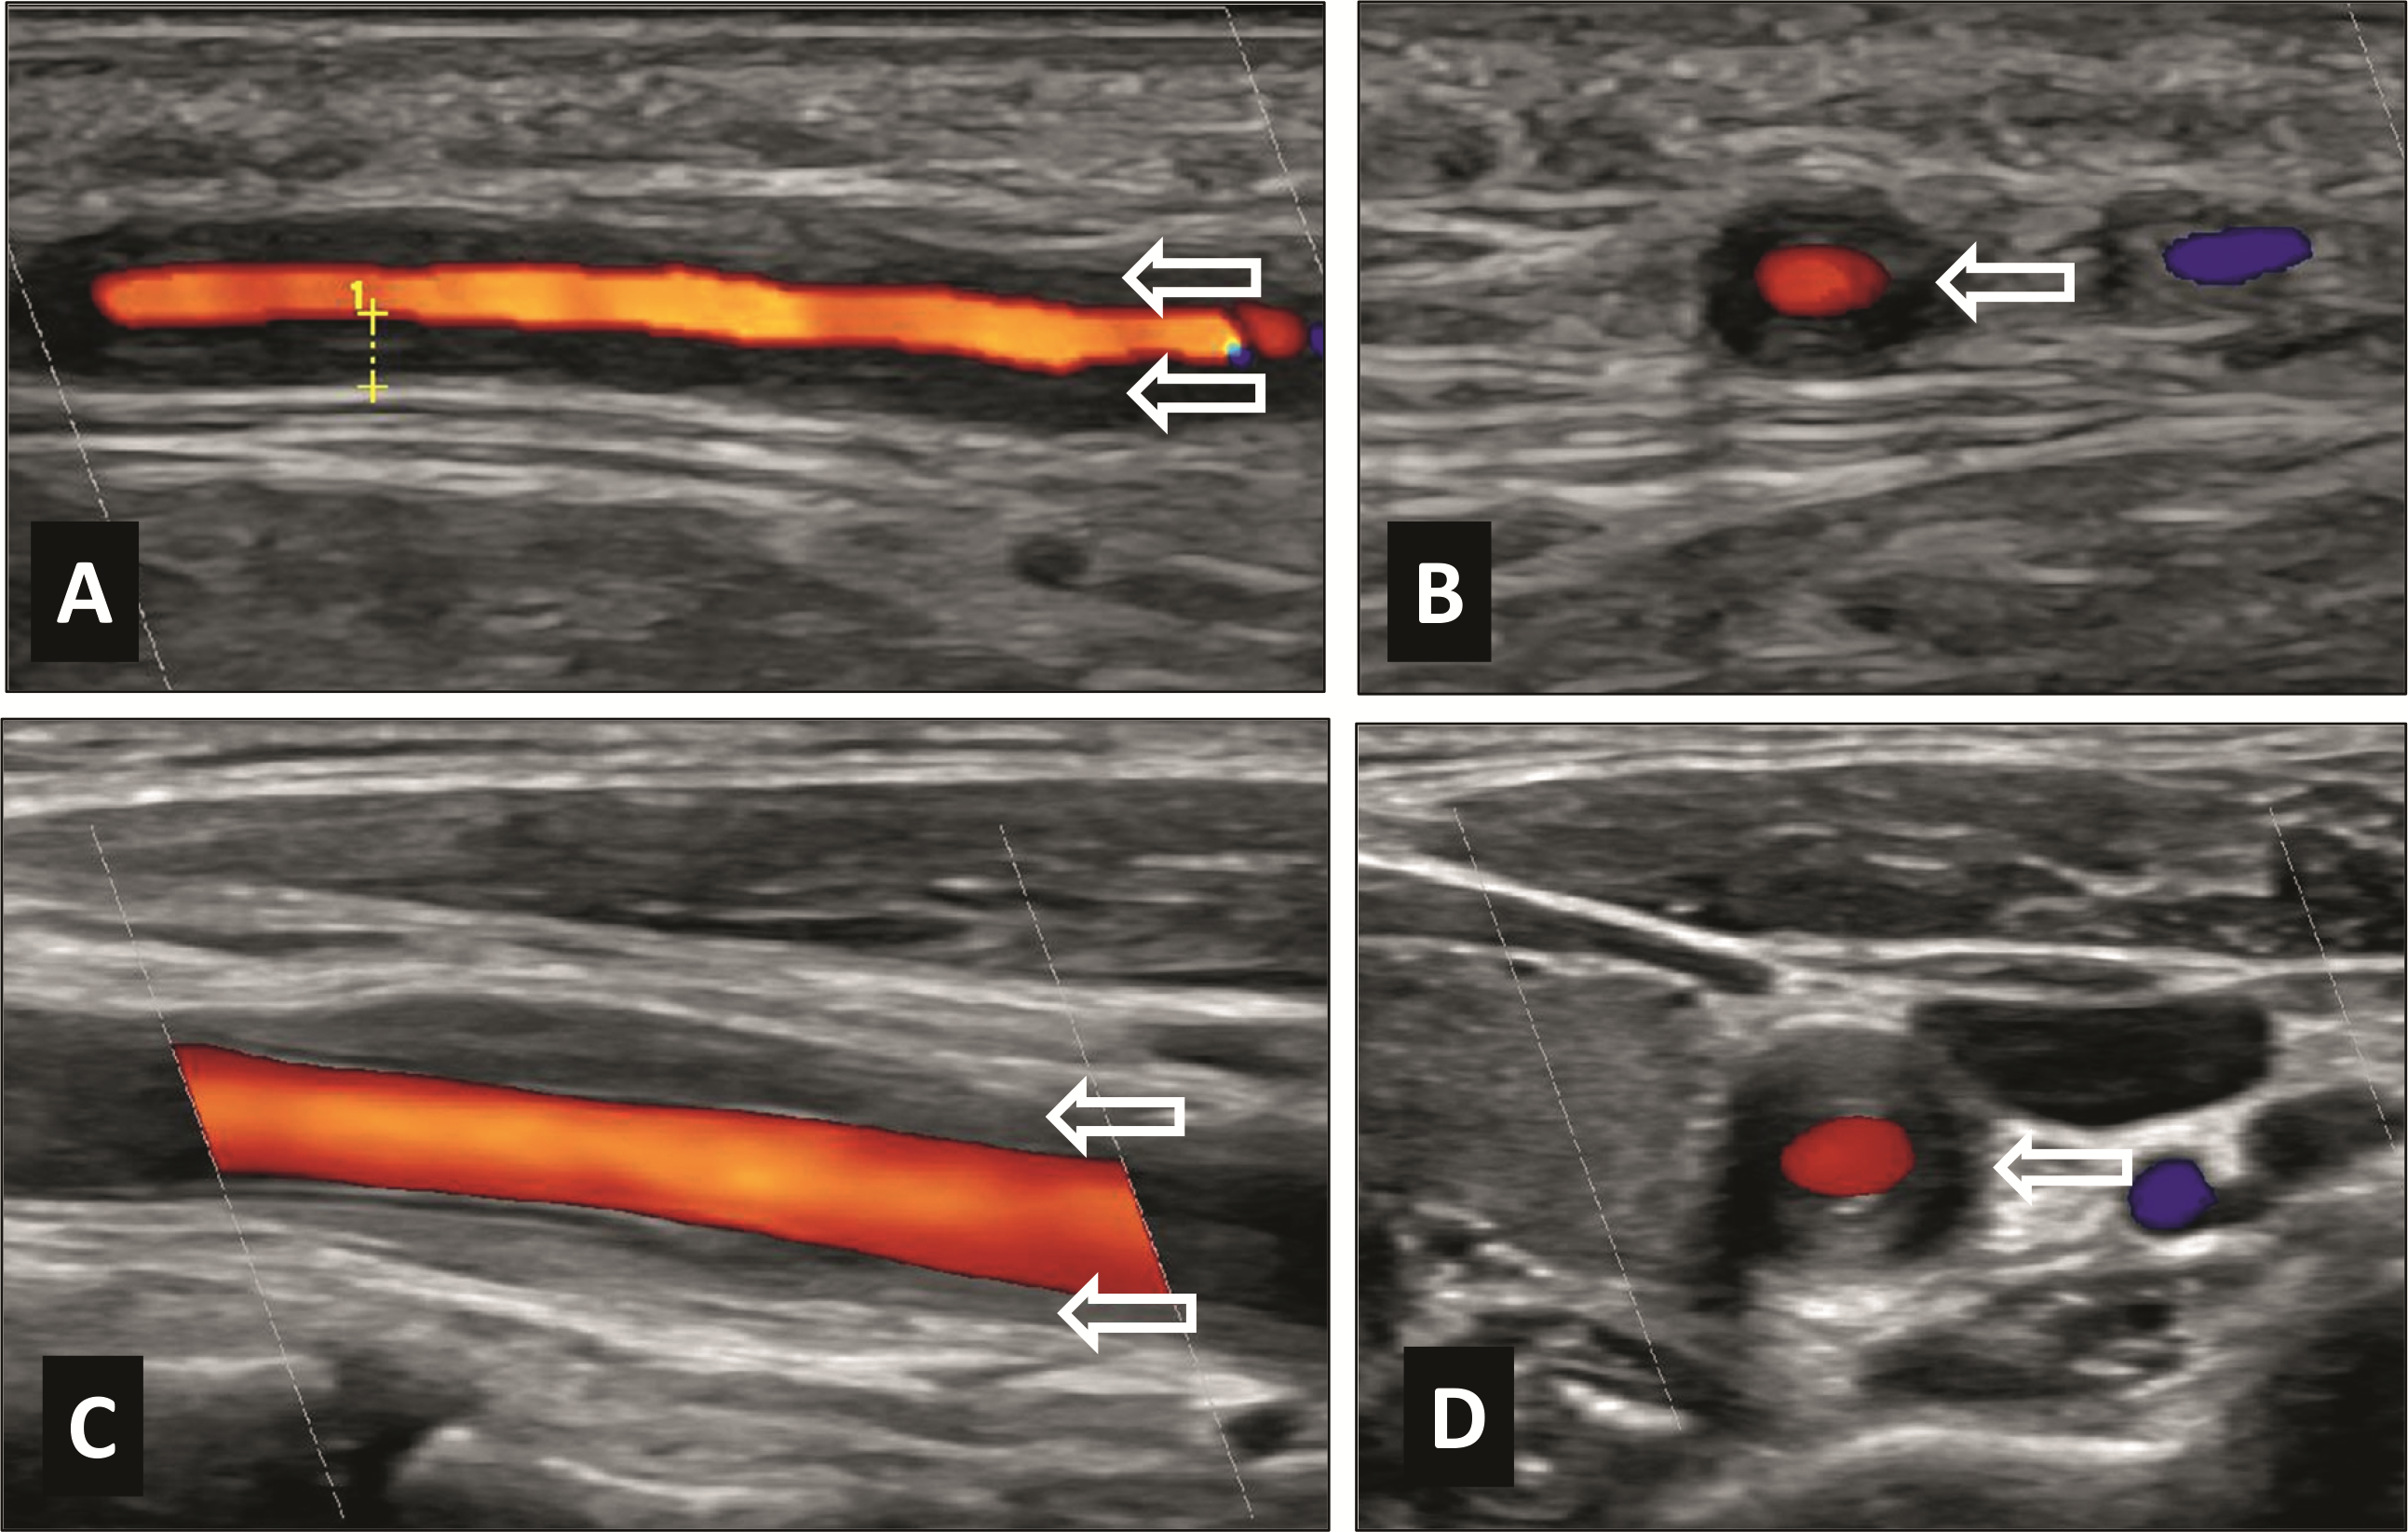

Die Diagnose einer Grossgefässvaskulitis sollte immer mittels Histologie und/oder Bildgebung objektiviert werden. Bei RZA-Verdacht wird die Temporalarterien-Biopsie (TAB) heutzutage in der Regel einseitig durchgeführt (Präparatlänge optimal > 1 cm) und wenn möglich innert zwei Wochen nach Beginn der GC-Therapie [35]. Zu beachten gilt, dass wegen des segmentalen Befalls eine negative TAB eine RZA nicht ausschliesst. Eine Histologie zur Diagnosesicherung der TAK ist nicht üblich. Neben der Histologie stehen mittlerweile eine Reihe an bildgebenden Verfahren zur Verfügung, die einzeln oder in Kombination eingesetzt werden: FDG-PET / CT, MRT / MR-Angiographie der Aorta, CT / CT-Angiographie und Ultraschall (Abb. 3). Fast-Track-Clinics und der schnelle Zugang zu Bildgebungen, wie der Ultraschalldiagnostik, erlauben eine raschere Diagnostik, was sich in einer besseren Prognose widerspiegelt [36]. Die Wahl der Bildgebung erfolgt unter Berücksichtigung der lokal vorhandenen Ressourcen und Patientenfaktoren (wie Kontraindikation für MR). Wichtig ist, dass relevante Strukturen dargestellt werden. Hierzu zählen insbesondere die A. carotis, A. subclavia und Aorta bei der TAK und die kraniellen, aber auch die grossen Gefässe inklusive Aorta bei der RZA.